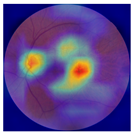

| No. | Fundus Image | Grad-CAM | Group | PRS | CNN | CNN+ML |

|---|---|---|---|---|---|---|

| 1 |  |  | Control | −2.13 | 0.63 | −0.34 |

| 2 |  |  | Control | −2.61 | 1.80 | −1.48 |

| 3 |  |  | AMD | 1.08 | 0.52 | −0.60 |

| 4 |  |  | AMD | −0.39 | −0.16 | −0.41 |